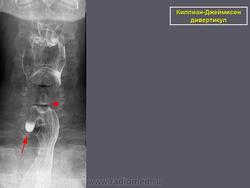

Киллиан – Джеймисон - дивертикул.

Приложения:

0.radiographics_logo.png0.rg_.337125153.fig15advustoronnyaya_killian-dzhemison_divertikulov_v_76-letney_zhenshchiny.gif0.rg_.337125153.fig15bdvustoronnyaya_killian-dzhemison_divertikulov_v_76-letney_zhenshchiny.gif